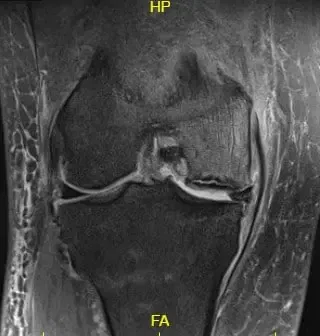

Los estudios de imagen revelaron osteoartritis severa en el compartimento medial de la rodilla derecha junto con artritis patelofemoral. La resonancia magnética reveló la progresión de una fractura subcondral previa en el cóndilo femoral medial, lo que ahora resulta en una región de necrosis avascular y una línea de fractura subcondral prominente llena de líquido que puede medir hasta 2,8 cm. Hubo un colapso leve del margen articular y un edema severo de médula ósea circundante.

Imagen ponderada T2 que muestra la sección coronal de la rodilla con señal alterada de la médula ósea y el signo del borde.